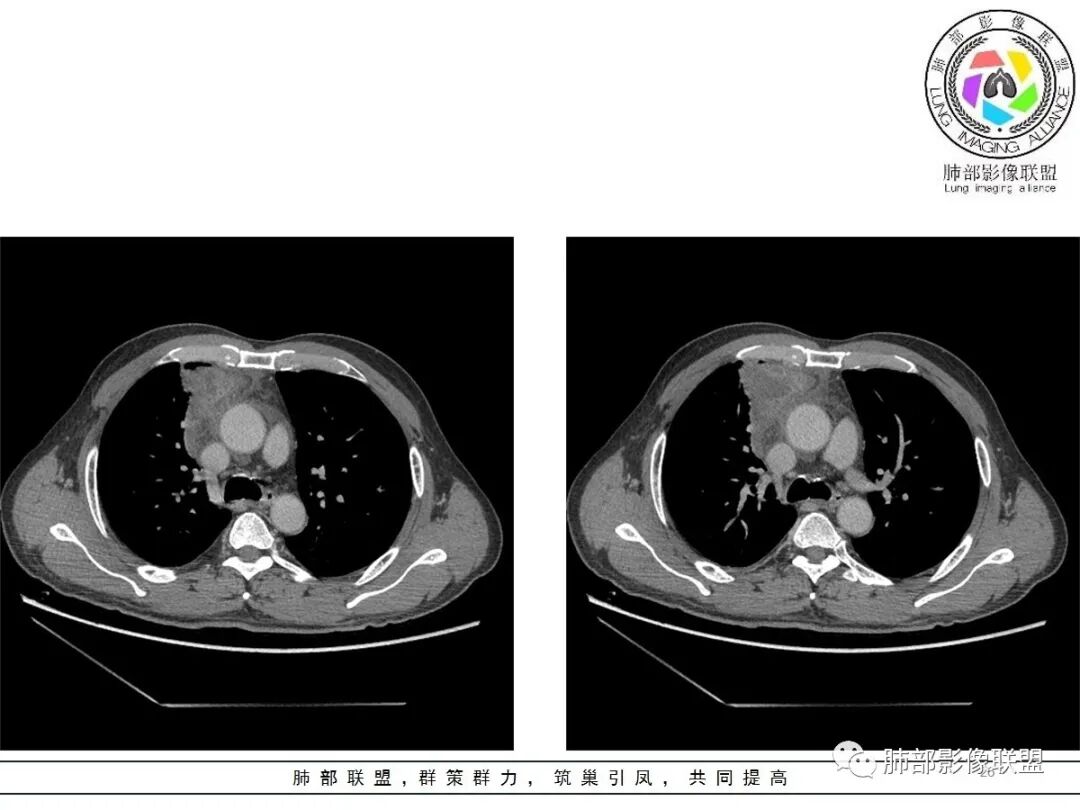

19日,4天后, 内部低密度影有,周围渗出增多,胸水增多

薄膜状强化

影像上周围病灶变化明显

常规肿瘤侵犯不支持,太快

应该是炎性病变渗出

脂肪密度明显,还有钙化、囊性病变,支持含脂质类病变破裂

周围是化学性炎症或出血所致

后期强化,可能与炎症有关

可能:1、肿瘤或瘤样病变破裂出血或内部物质外溢所致2、炎性病变所致

4.四天内病灶变化快,块影增大且不规则,包膜似不完整,边界不清,上份可见浸润或渗出,与周围心脏大血管及心包等间隙不清。胸水增多。

第一次的检查符合胸腺瘤影像学改变,短期内的形态学改变及突然出现的边界模糊或浸润等,符合出血或炎症。